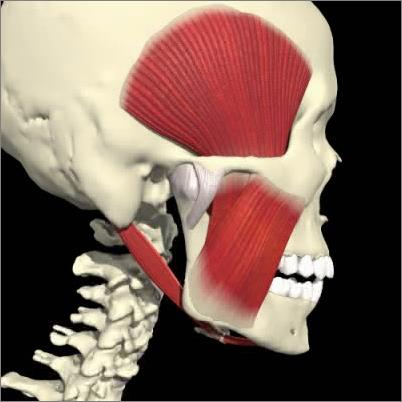

Patologie A.T.M.

L'articolazione temporo mandibolare (ATM) è un'articolazione molto complessa e la sua patologia, causata da disfunzioni muscolari cinetiche (del movimento masticatorio) puo' interessare sia la componente ligamentosa/meniscale (lussazione, sublussazione , incoordinazione meniscale , lassità ligamentosa) , che la componente ossea(artriti , artrosi ). L'ATM è al centro di un complesso sistema che coinvolge ossa-muscolo e denti e quindi una sua patologia pu' determinare ripercussioni molto importanti ed invalidanti di piu' apparati . Per i motivi sopra citati è molto importante diagnosticare precocemente e con estrema accuratezza specialistica (esame gnatologico) i disturbi e le disfunzioni neuro-muscolari dell'atm che molto spesso necessitano di un approccio multidisciplinare (reumatologo, neurologo, fisioterapista...). Nei nostri centri è disponibile la figura dello gnatologo atto alla diagnosi e alla eventuale terapia di queste patologie .

![]() | ![]() | ![]() |